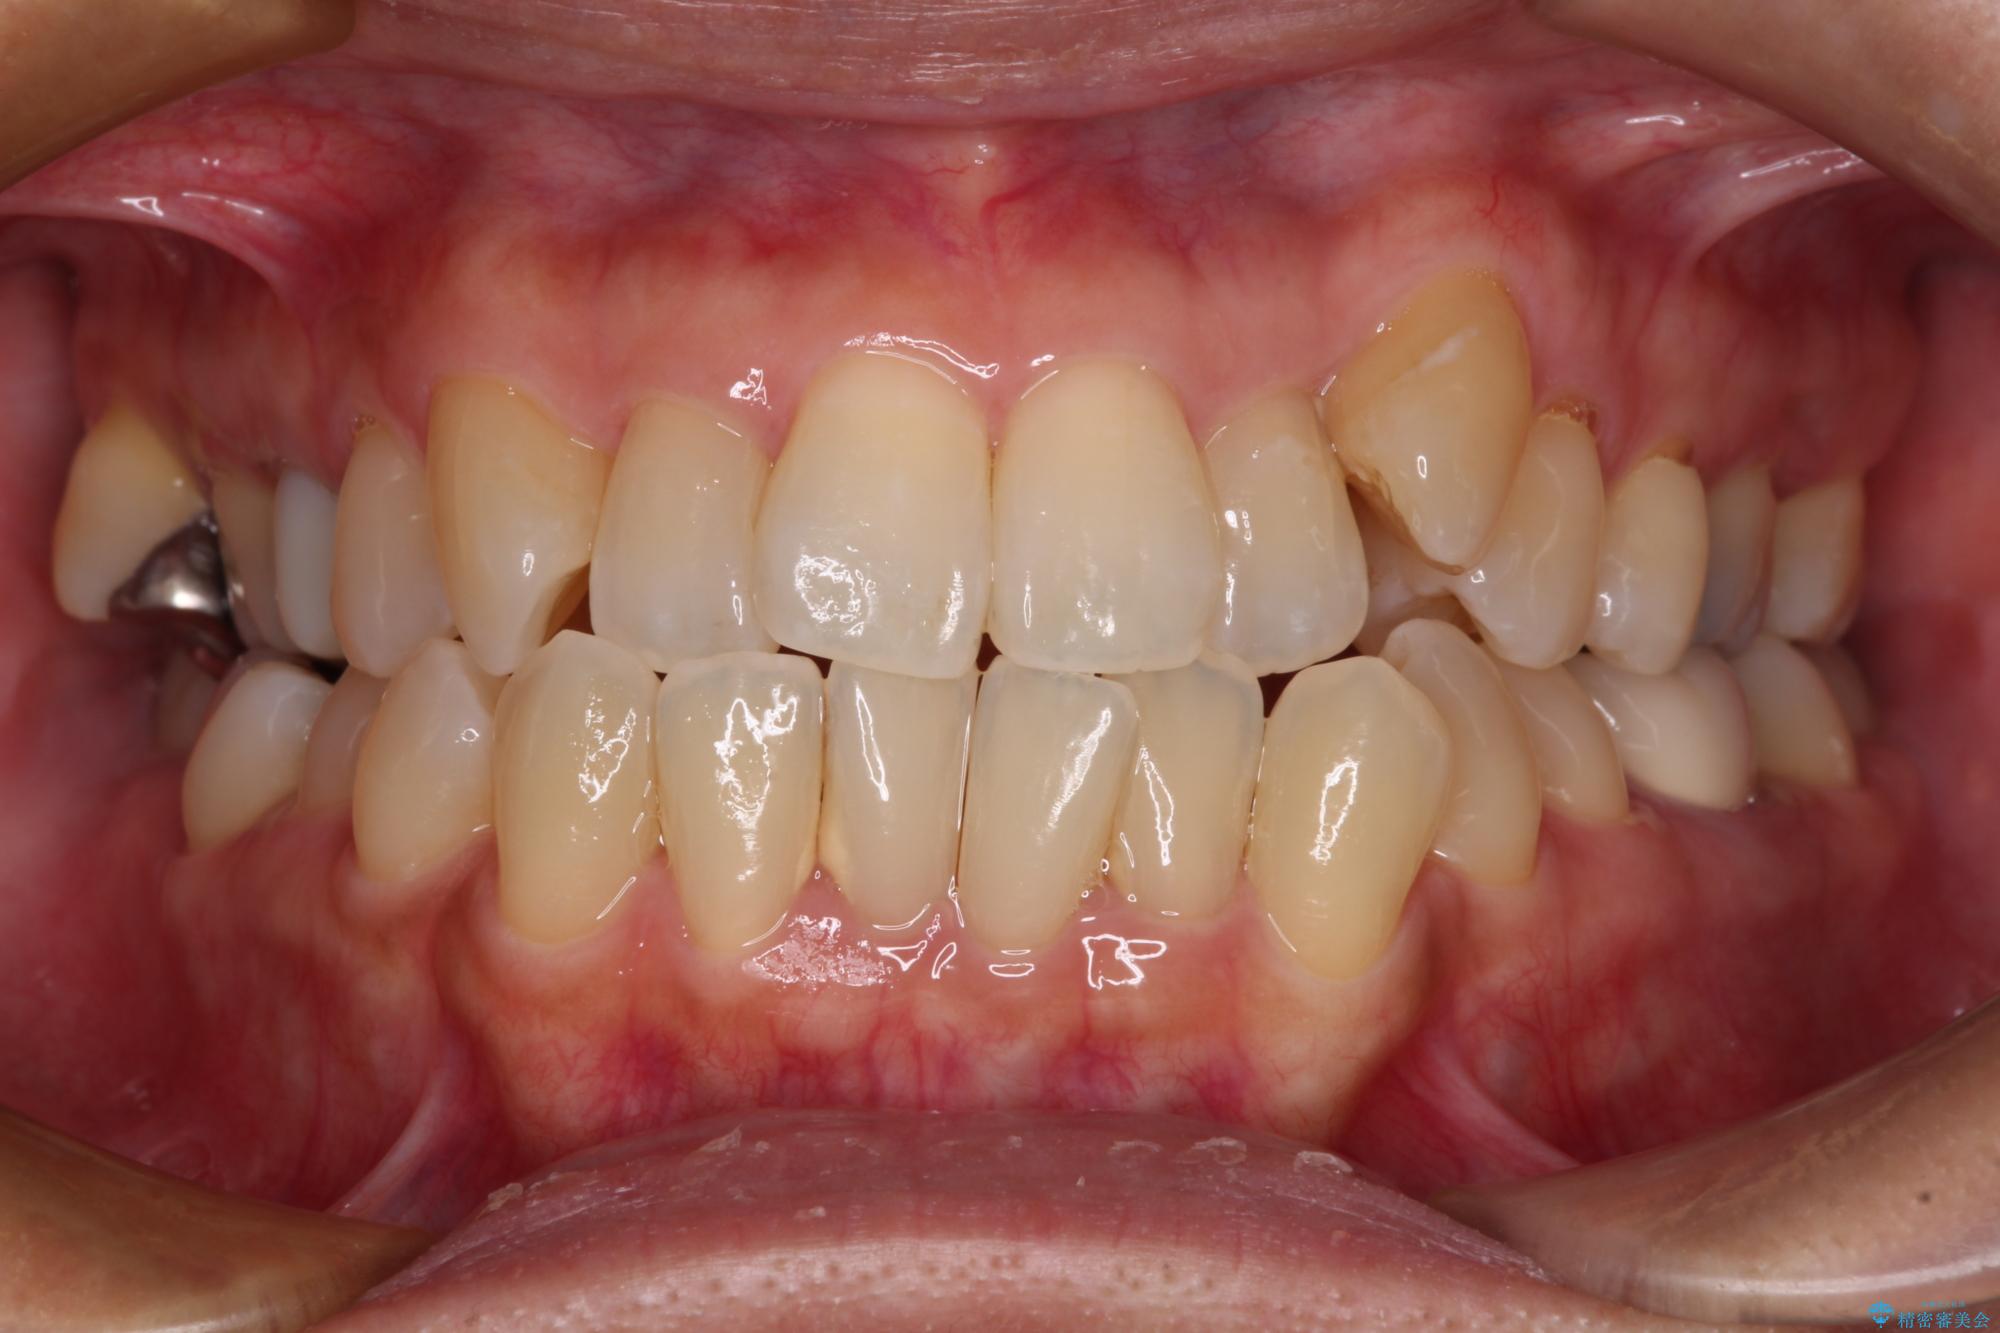

- 前歯のデコボコや八重歯を治したいとのことで来院された患者様です。

受け口傾向の骨格であり、前歯はクロスバイトまたは切端咬合となっており、下顎を中心に歯列全体の後方移動を行い、IPR(歯と歯の間を削る)によってデコボコが解消するように設計し、インビザラインにより治療を行うこととしました。

受け口傾向のインビザライン矯正は比較的治療を行いやすいため、きれいに仕上げることができました。舌の突出癖が顕著であったため、改善のためのトレーニングをしっかりと行っていただきました。